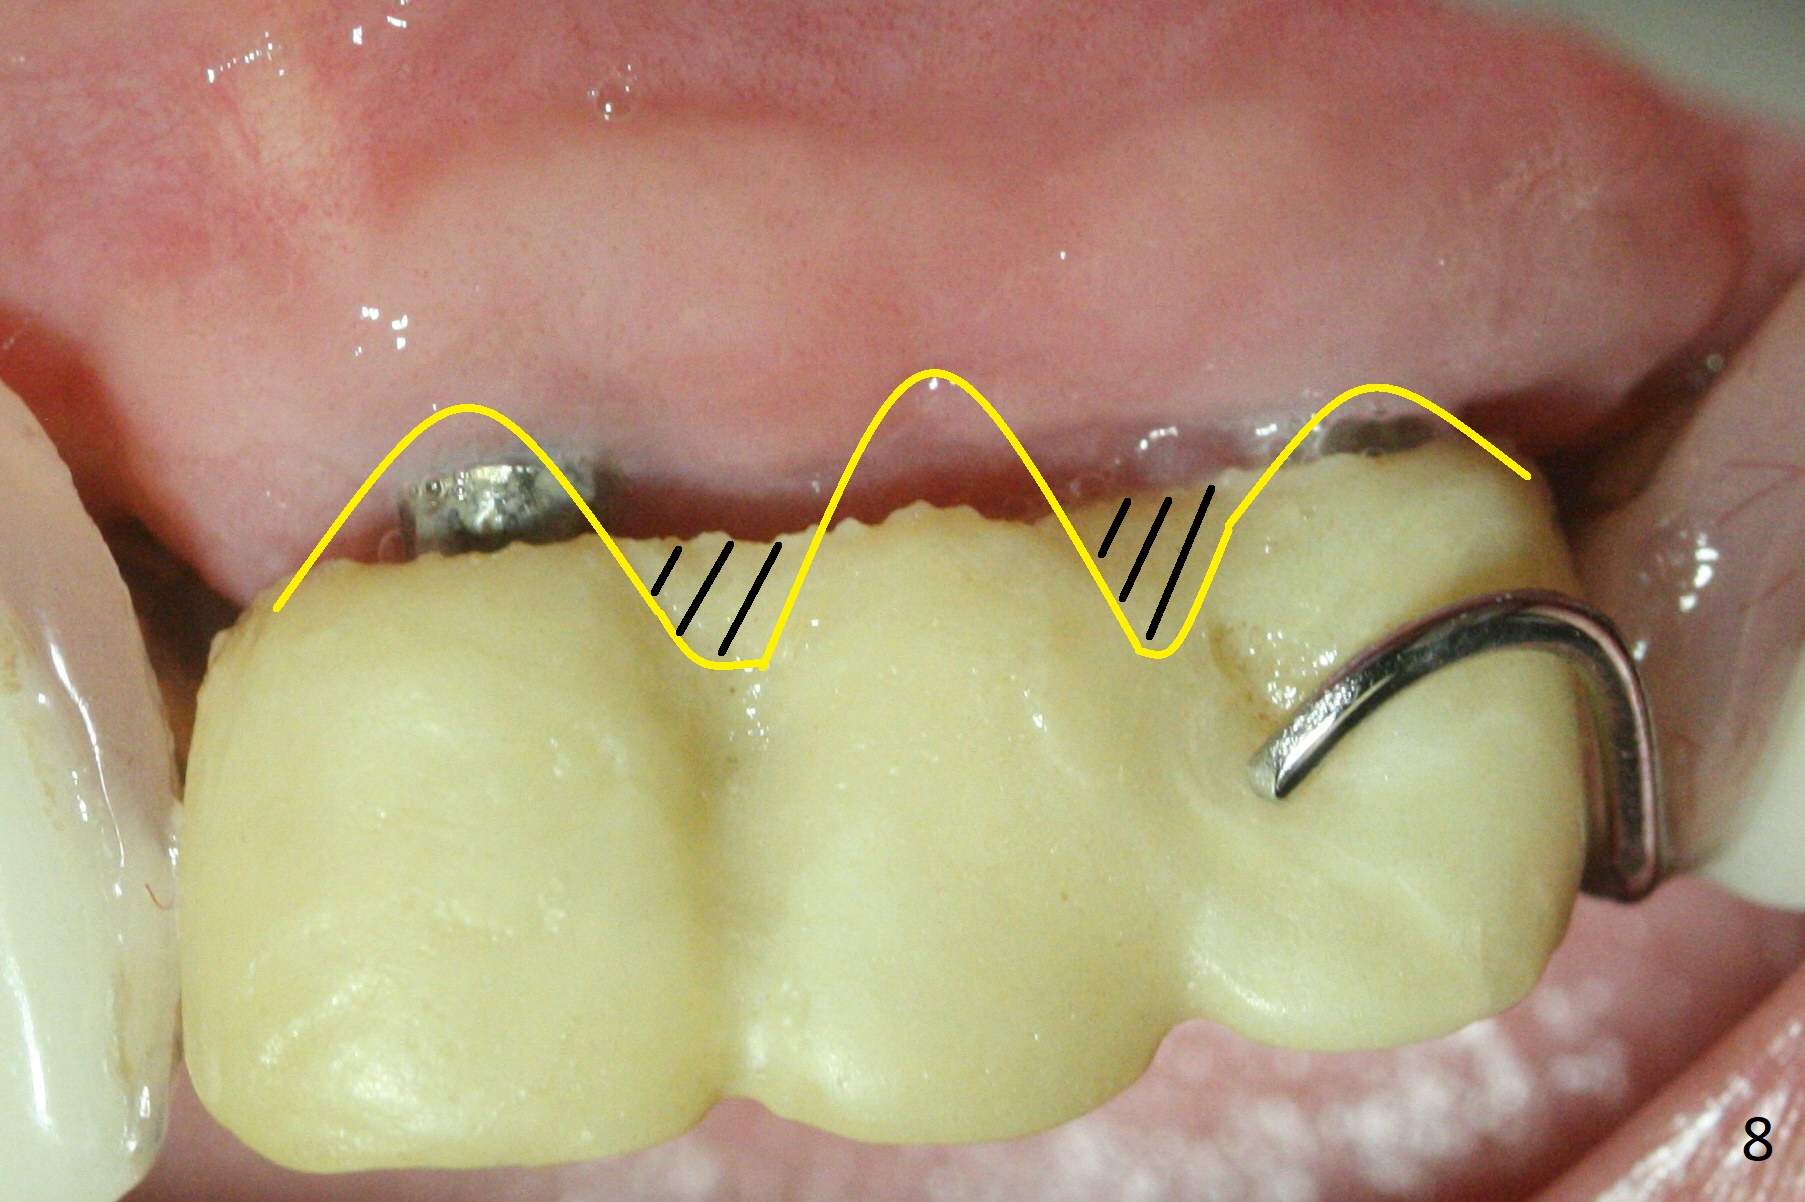

Incision reveals that the ridge at #9 and 11 is narrower than expected. A 3x14 mm 15º 1 piece implant is placed at the site of #9, while a 3x17 mm straight 1-piece one is placed at #11 (Fig.1,4). Insertion torques at #9 and 11 are 20 and 30 Ncm, respectively. The relatively low insertion torque is partially due to osteoporosis. The 65-year-old lady also has dry mouth. Osteotomy should be underprep. The position and trajectory of the implants are dictated by the partial denture (Fig.2). After minor abutment adjustment (Fig.3), an immediate provisional bridge is fabricated. There is no interference when the partial is removed and inserted. After bone graft (Fig.4 ^) and Osteogen Membrane, the ridge (Fig.3) is wider than before. The patient returns for reline 2 months postop (Fig.5-7). In spite of insufficient oral hygiene, the gingiva remains healthy around the implants. To form distinct papillae, acrylic should be added to (Fig.8 yellow line) and removed from (hushed area) the individual provisional crowns. One month after provisional modification (Fig.10, as compared to Fig.5), the pontic recipient site is concave (Fig.11) and becomes less concave after cord packing and abutment trimming. When the provisional bridge is reseated after impression (Fig.12), the pontic recipient site must be blanched again. Please trim the pontic recipient site of the model ~ .5 mm to enhance cosmetics. Water Pik has been used since surgery, but it may be related to loss of bone graft 3.5 months postop (Fig.9 *). One month post cementation, the patient has complained of pain when water pik is irrigating the gingiva palatal to the FPD, apparently in association with denture-related Candidiasis. Two weeks of use of Mycostatin Oral Suspension, peri-implantitis or peri-implant mucositis-like signs and symptoms disappear (Fig.13). CBCT taken 6 months postop confirms that the implants appear to be have been placed in the bone (14,15). The FPD appears to be loose 2.5 years post cementation.